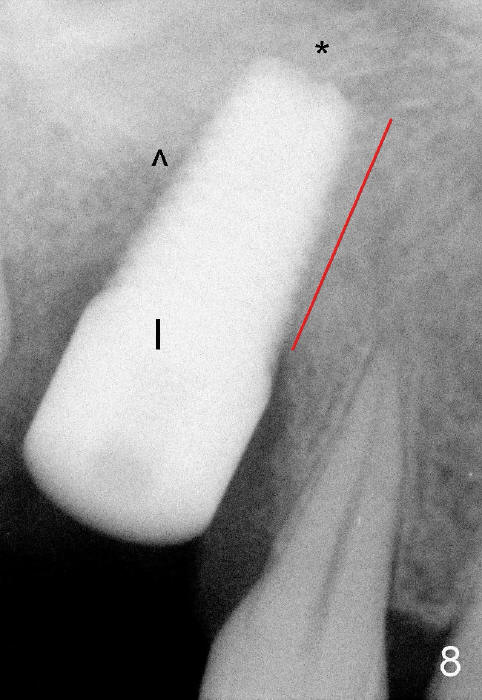

It appears that when a 7x17 mm implant is placed (Fig.8), the bone contact is increased vertically (red line) as the diameter of the implant increases. ^: sinus floor; *: bone present apical to the implant.